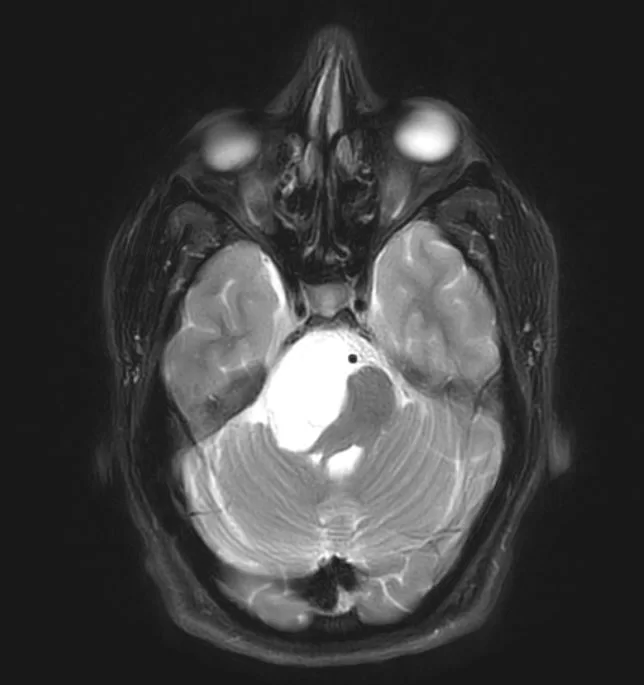

Ο απεικονιστικός έλεγχος με μαγνητική τομογραφία ανέδειξε ευμεγέθη εξεργασία στη δεξιά γεφυροπαρεγκεφαλιδική γωνία.